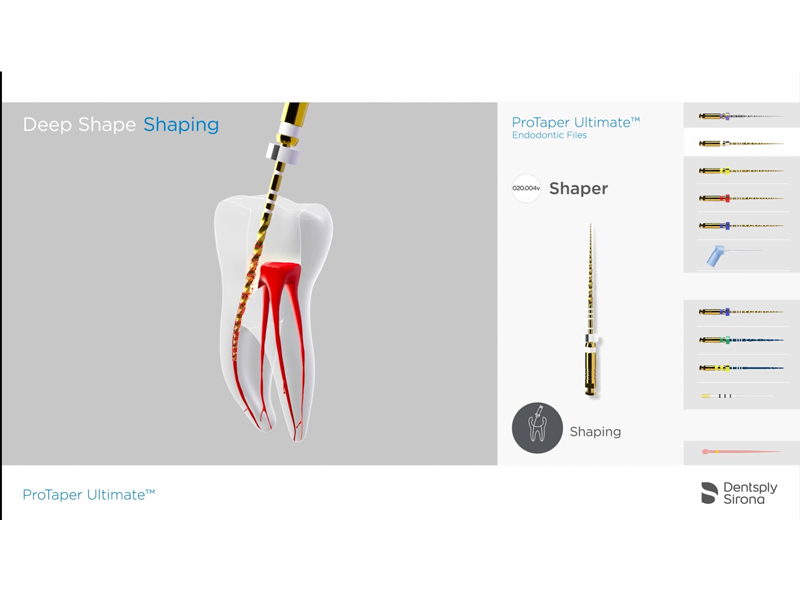

POINT治療の成功率を支えるニッケルチタンファイル・根管長測定器

従来のステンレス製ファイルは硬度が高いため、大きく湾曲していたり、狭くなっていたりする難易度の高い根管では、歯の組織を過剰に削ってしまうリスクがありました。

それに対し、当院で採用しているニッケルチタンファイルは、形状記憶特性と優れた柔軟性を併せ持ちます。この特性により、複雑な根管の形状に沿ってしなやかに進み、歯質へのダメージを最小限に抑えながら、根の先端隅々まで感染源を精密に除去することが可能です。

また、専用の根管拡大装置に装着して使用することで、治療の効率と精度が向上し、患者様の負担軽減や治療時間の短縮にも繋がります。